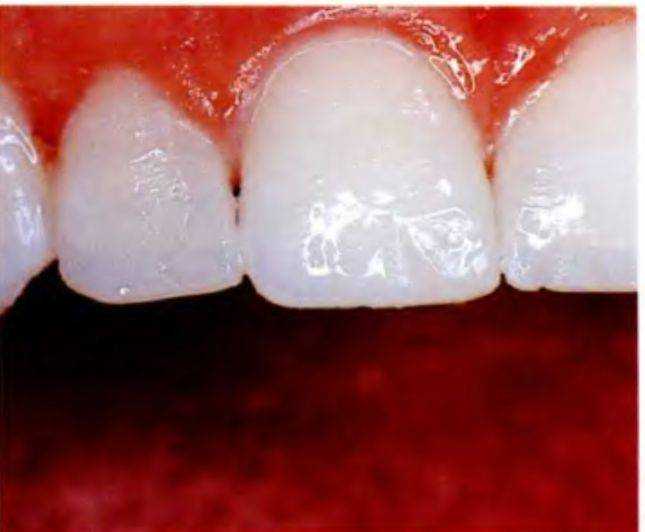

Далее были выполнены финишная обработка и полирование реставраций. Вся работа проводилась как можно более аккуратно во избежание повреждения естественных тканей зуба (рис. с 6-12t по 6-12х). Диагностические реставрации должны быть

обратимыми, т.е. выполнены без препарирования зубов.

Окончательная оценка реставрации была проведена в положении пациентки лежа и спереди (рис. 612у). На данном этапе основная ошибка может заключаться в том, что стоматолог просто дает пациенту маленькое зеркало и спрашивает: «Ну, как Вам нравится?» Результат же следует оценивать в целом с помощью большого зеркала, в котором отражается все лицо пациента. Причем пациент должен подойти к зеркалу, а стоматолог может оценить его реакцию на результат. В данном случае пациентка осталась очень довольна (рис. 6-12z и 6-12аа).

Впоследствии были изготовлены фотографии с диагностическими реставрациями и без них. Кроме того, рекомендуется получать оттиски диагностических реставраций для облегчения коммуникации с зубным техником и предоставления ему информации о желаемом результате.